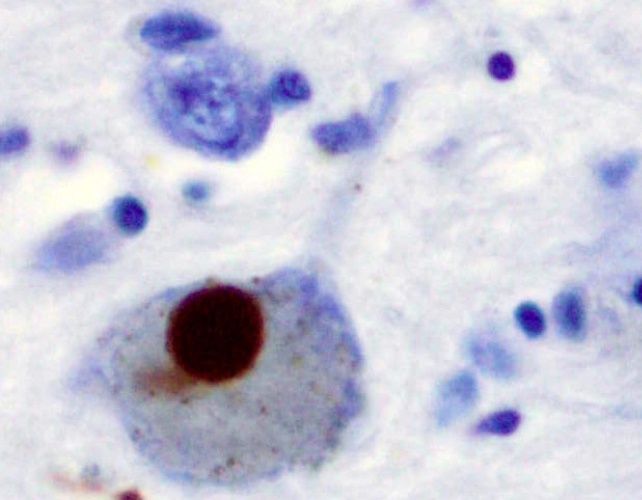

تحقیقات نشان میدهد که آلفا-سینوکلئین معمولاً ارتباط عملکردی بین نورونها را حفظ میکند، اما زمانی که این پروتئین دچار تغییر شکل میشود، مشکلاتی ایجاد میشود. در آزمایشات اخیر، محققان متوجه شدند که حذف همزمان پروتئینهای Aplp۱ و Lag۳، به طور قابل توجهی جذب آلفا-سینوکلئین را در مغز موشها کاهش میدهد.